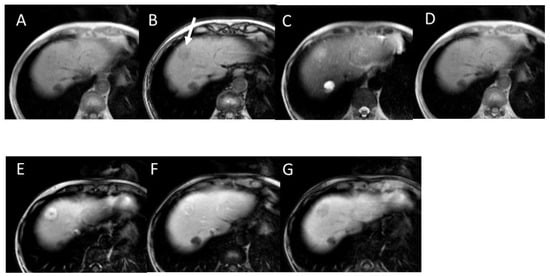

- Okada, M.; Nakamura, Y.; Kuwatsuru, R.; Nakamura, Y.; Isoda, Y.; Goshima, S.; Hanaoka, R.; Haradome, H.; Shinagawa, Y.; Kitao, A.; et al. Biochemical and Clinical Predictive Approach and Time Point Analysis of Hepatobiliary Phase Liver Enhancement on Gd-EOB-DTPA–enhanced MR Images: A multicenter study. Radiology 2016, 281, 474–483. [Google Scholar] [CrossRef]

- Katsube, T.; Okada, M.; Kumano, S.; Hori, M.; Imaoka, I.; Ishii, K.; Kudo, M.; Kitagaki, H.; Murakami, T. Estimation of liver function using T1 mapping on Gd-EOB-DTPA-enhanced magnetic resonance imaging. Investig. Radiol. 2011, 46, 277–283. [Google Scholar] [CrossRef]

- Tokorodani, R.; Kume, T.; Daisaki, H.; Hayashi, N.; Iwasa, H.; Yamagami, T. Combining 99mTc-GSA single-photon emis-sion-computed tomography and Gd-EOB-DTPA-enhanced magnetic resonance imaging for staging liver fibrosis. Medicine 2023, 102, e32975. [Google Scholar] [CrossRef]